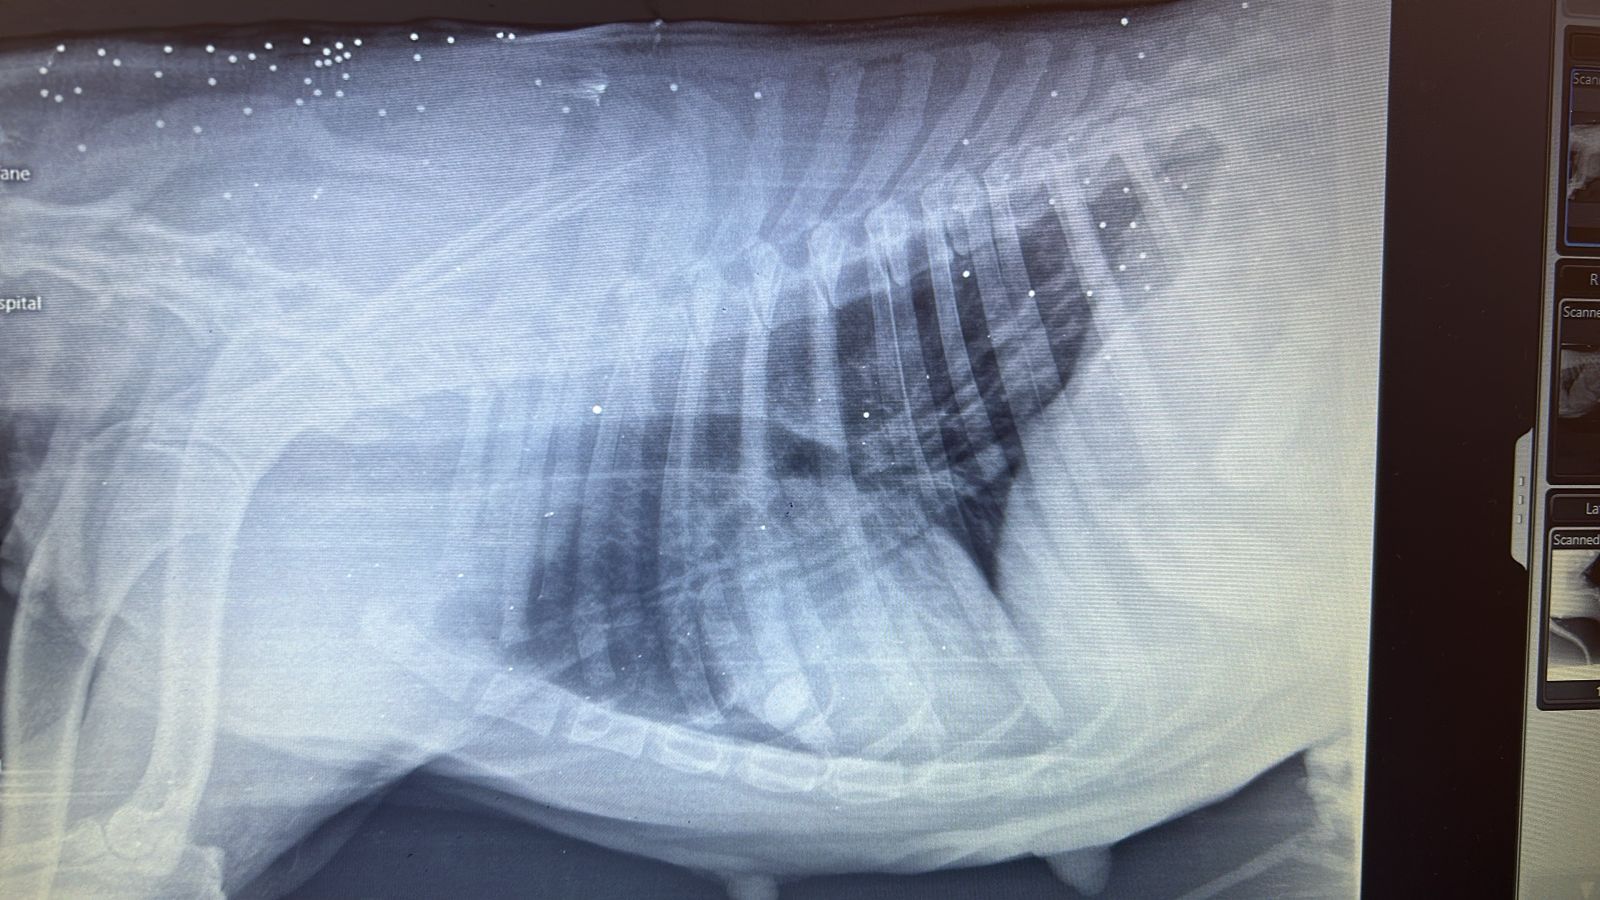

Peaches was rescued from Ramlet el Bayda. She was shot by an official from the municipality. Her leg was completely shattered. We had to amputate! She’s very mellow, sweet and is good with other dogs. DOB: 8/8/2017